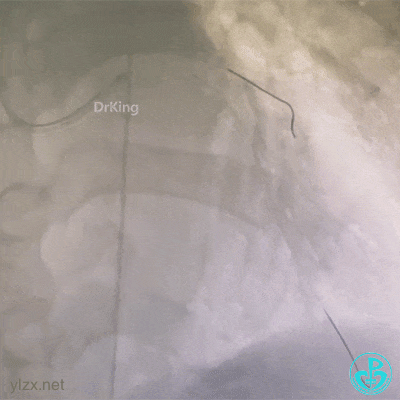

2 急诊冠脉造影

造影示前降支近端闭塞。

造影前有创血压(80~90)/(40~58)mmHg,造影后下降至(60~70)/(40~50)mmHg。

EBU 3.5指引导管到位,导丝分别进入前降支和回旋支。

2.0×15mm球囊扩张后前降支恢复2级血流,前降支近段血栓影,经指引导管推注尿激酶原20mg。

复查造影示残余狭窄仍重,近段植入3.75×20mm支架。

冠脉内推注替罗非班10ml,血流恢复TIMI 3级,结束手术。